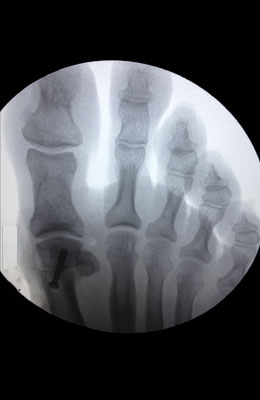

Osteotomy Bunionectomy, Hammertoe Correction and Plantar Plate Repair after

Osteotomy Bunionectomy, Hammertoe Correction and Plantar Plate Repair

Ziba is a 67-year-old female with years of foot pain. Her bunion was so severe she had placed a lot of weight on her 2nd and 3rd toes which had become totally dislocated (as shown in x-rays). Ziba required an osteotomy bunionectomy, hammertoes corrections with our Ossio™ implant and metatarsal phalangeal joint relocation and plantar plate repair. Ziba was allowed to place weight on her foot right after surgery and was back in shoes at 8 weeks. An amazing result considering how difficult toe relocation can be. After picture taken immediately following surgery.